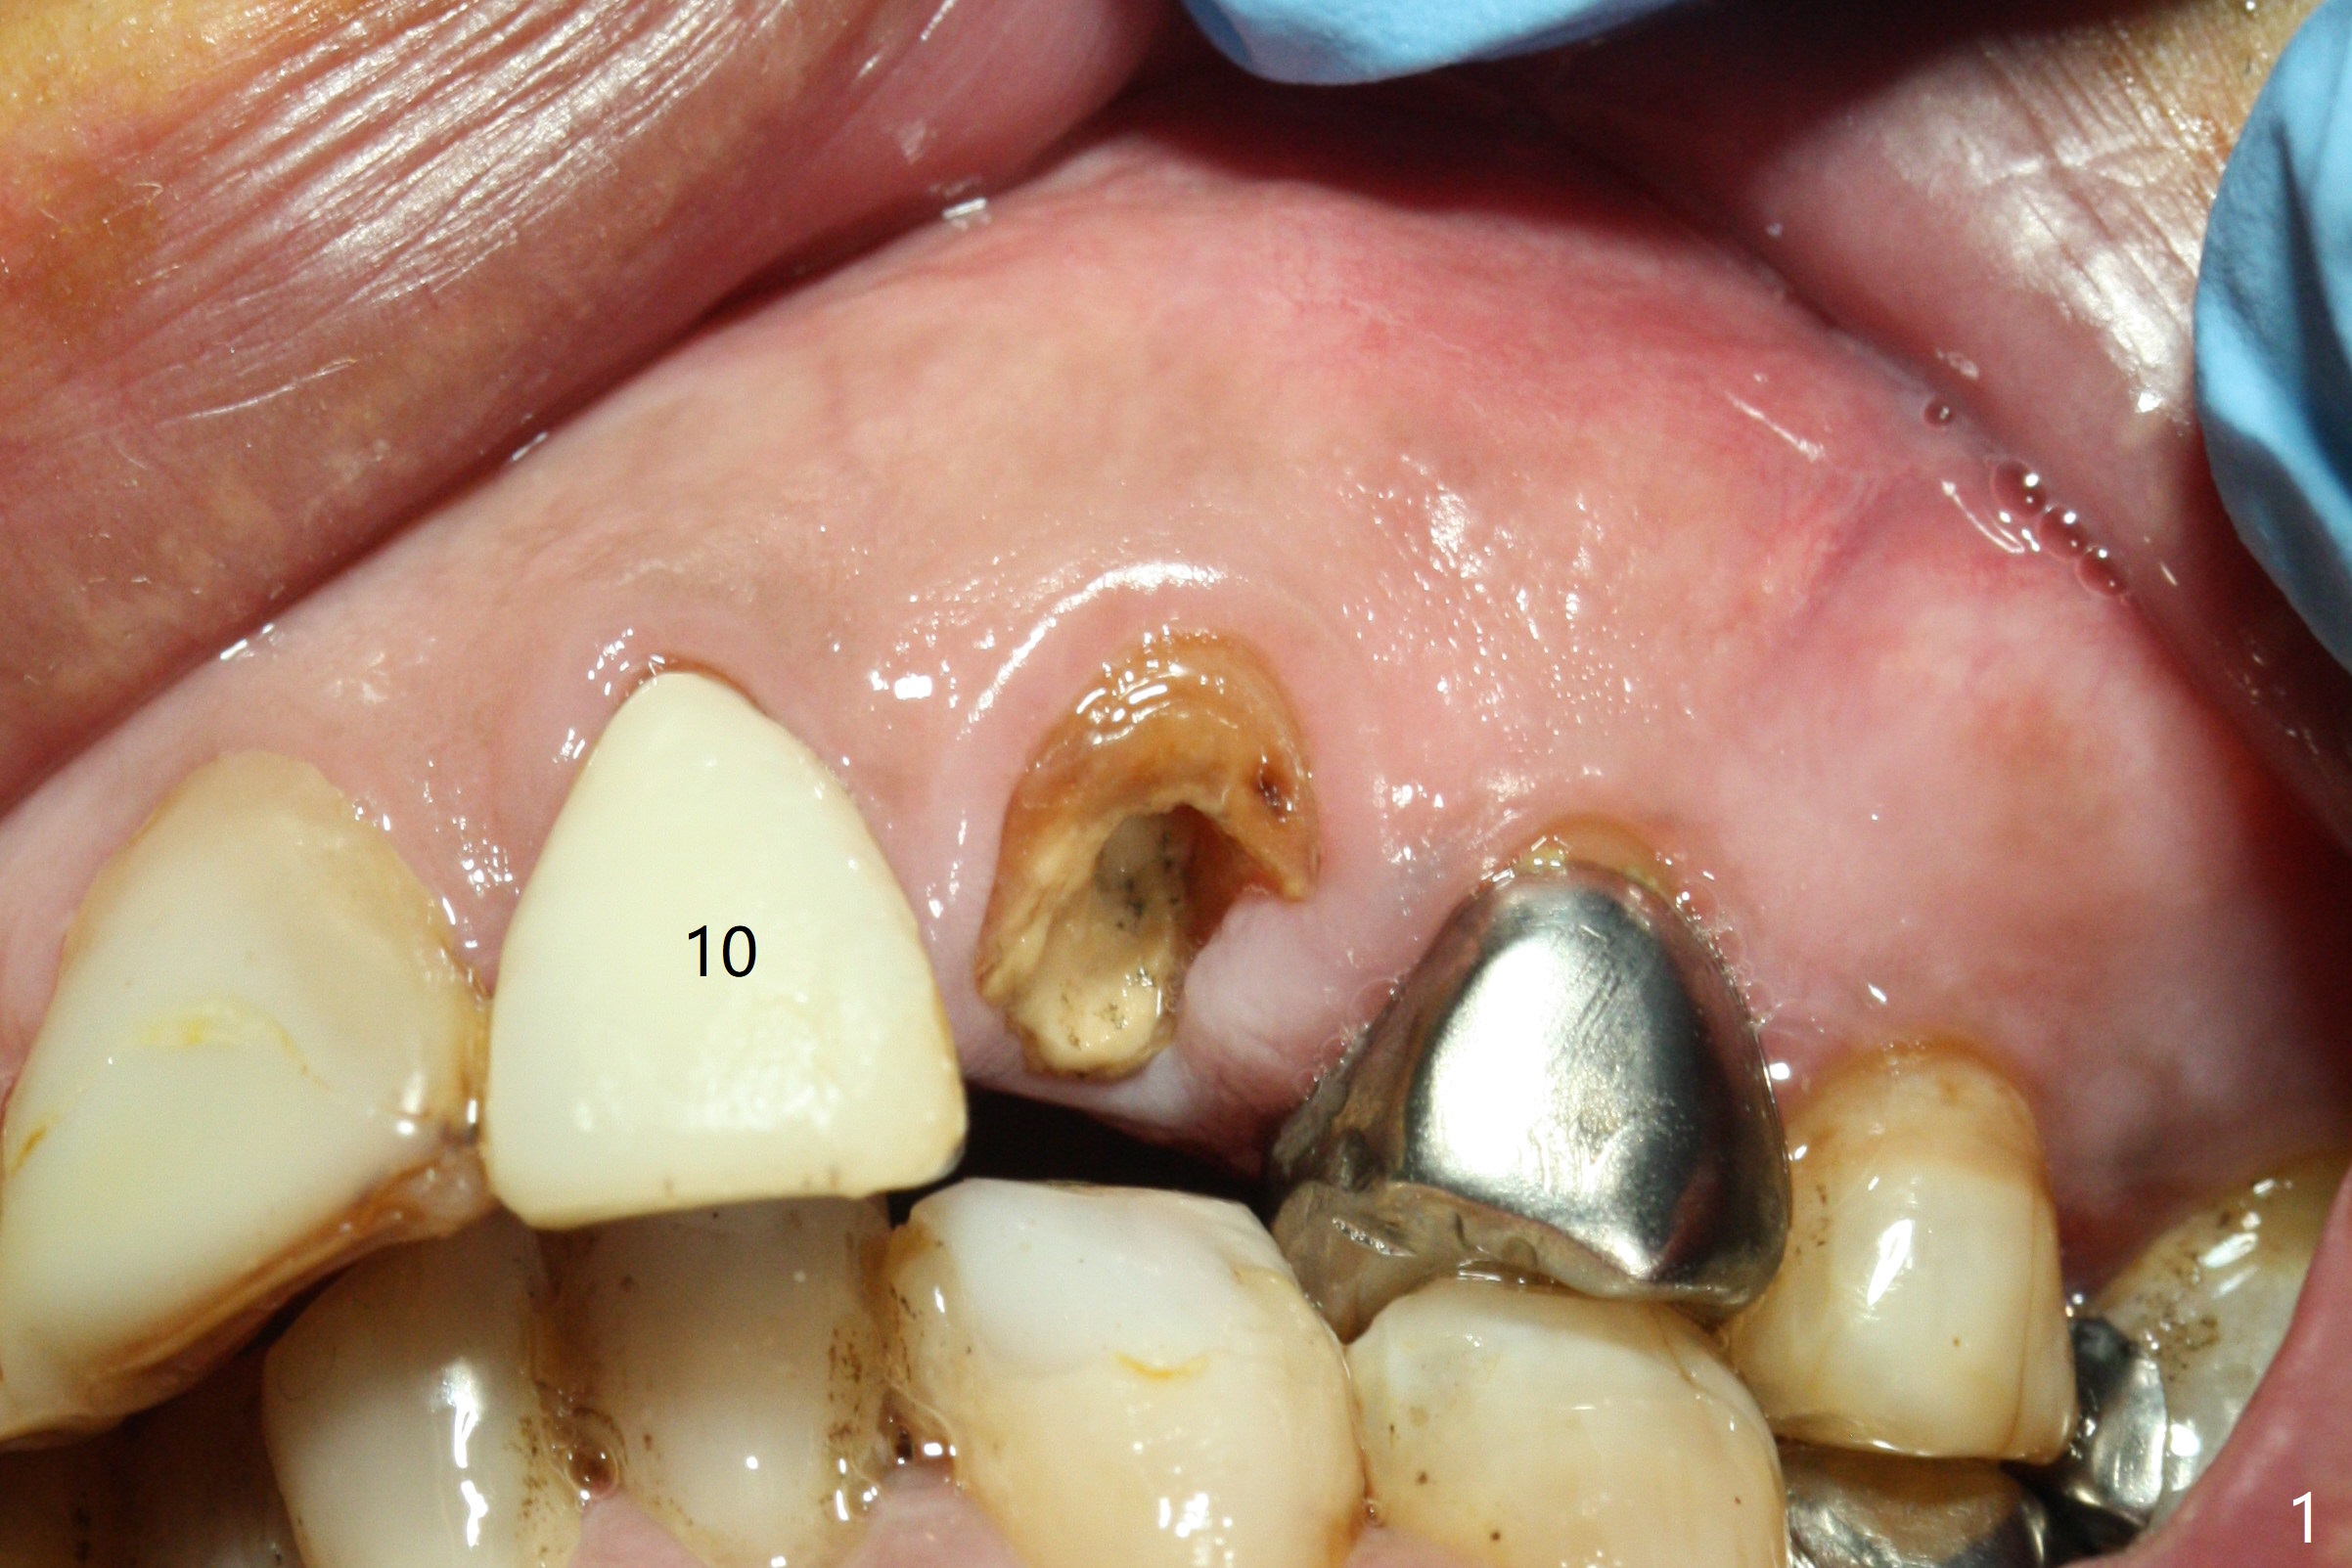

Extraction of the residual root at #11 (Fig.1) turns out to be difficult (Fig.2 (arrow: after use of small elevator). The tooth is sectioned (Fig.2 *); the palatal portion is removed, while the buccal one is trimmed until new moon-shaped and subgingival (Fig.3 * (gauze (G) packed in the socket while photo taking)). Initial osteotomy is 20 mm deep with nasal floor perforation (Fig.4). The subsequent depth is 17 mm (Fig.5). When a 5x17 mm tissue-level implant is placed (Fig.6,7; >60 Ncm), there is a gap between it and the socket shield (Fig.6 *). Gap-filling Vera Graft (Fig.8 *) also covers the shield prior to fabrication of an immediate provisional (Fig.9). There is no apparent bone loss 3.5 months postop (Fig.10). There is no buccal plate resorption 9 months postop (Fig.11). The implant is doing well 2 years postop (1 year 9 months post cementation, Fig.12).